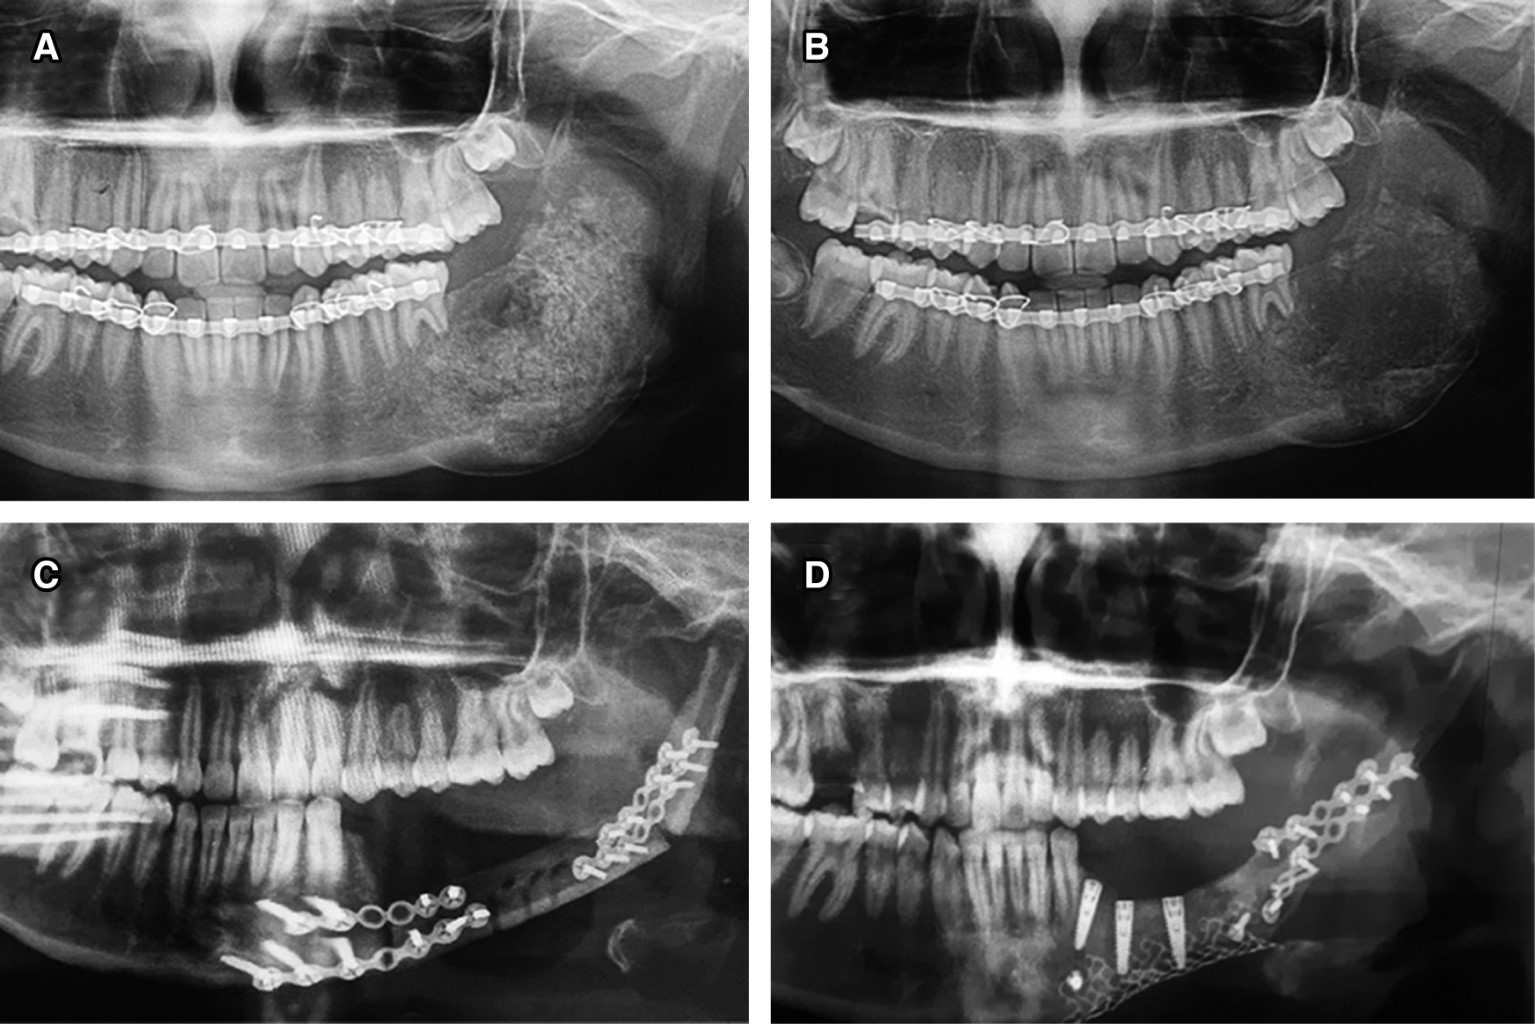

Radiográficamente, la ortopantomografía (OPG) evidenció una gran lesión radiolúcida multilocular, expansiva, con bordes escleróticos y diminutas zonas radiopacas, con reabsorción radicular del OD 35 y 36, así como desplazamiento del OD 37 hacia el borde basal mandibular (Figura 1B). Por las características clínicas, radiográficas y el involucramiento de un OD, el diagnóstico diferencial incluyó una lesión de origen odontogénico benigna como quiste dentígero, queratoquiste odontogénico y FA. Bajo anestesia general y con intubación orotraqueal, se procedió a la enucleación y curetaje de la lesión, que mostró características fibrosas y se desprendía en porciones (Figura 1C), el OD 37 también se extrajo. Después se colocó injerto alógeno, la paciente se revirtió sin complicaciones y fue dada de alta siete días después.

Dos meses después de la cirugía, se solicitó una OPG para el control radiográfico, sin evidencia de alteraciones (Figura 3A). A los seis meses de seguimiento, una OPG evidenció una zona radiolúcida mal definida, con bordes irregulares, en el área del injerto óseo (Figura 3B), se interpretó como persistencia de la lesión y se remitió a la paciente al Centro Médico de Pediatría del IMSS, UMAE, en la ciudad de Guadalajara, Jalisco, para un tratamiento quirúrgico radical, que consistió en una resección mandibular con colocación de placas de titanio e injerto microvascularizado de peroné (Figura 3C).

Ocho meses después, extraoralmente se observó ligera asimetría facial (Figura 4A). Al realizar el examen intraoral, se observó la mucosa en condiciones normales (Figura 4B). Después de 30 meses de seguimiento, la paciente se encuentra libre de lesión y en proceso de rehabilitación oral mediante la colocación de implantes, con el objetivo de devolver la función masticatoria y estética (Figura 3D).